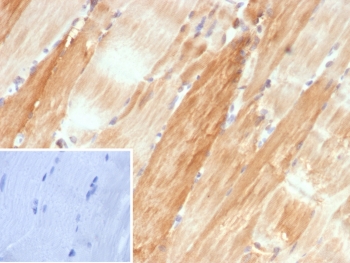

IHC staining of FFPE human skeletal muscle tissue with Crystallin Alpha B antibody (clone CRYAB/4662). Inset: PBS used in place of primary Ab (secondary Ab negative control). HIER: boil tissue sections in pH 9 10mM Tris with 1mM EDTA for 20 min and allow to cool before testing.